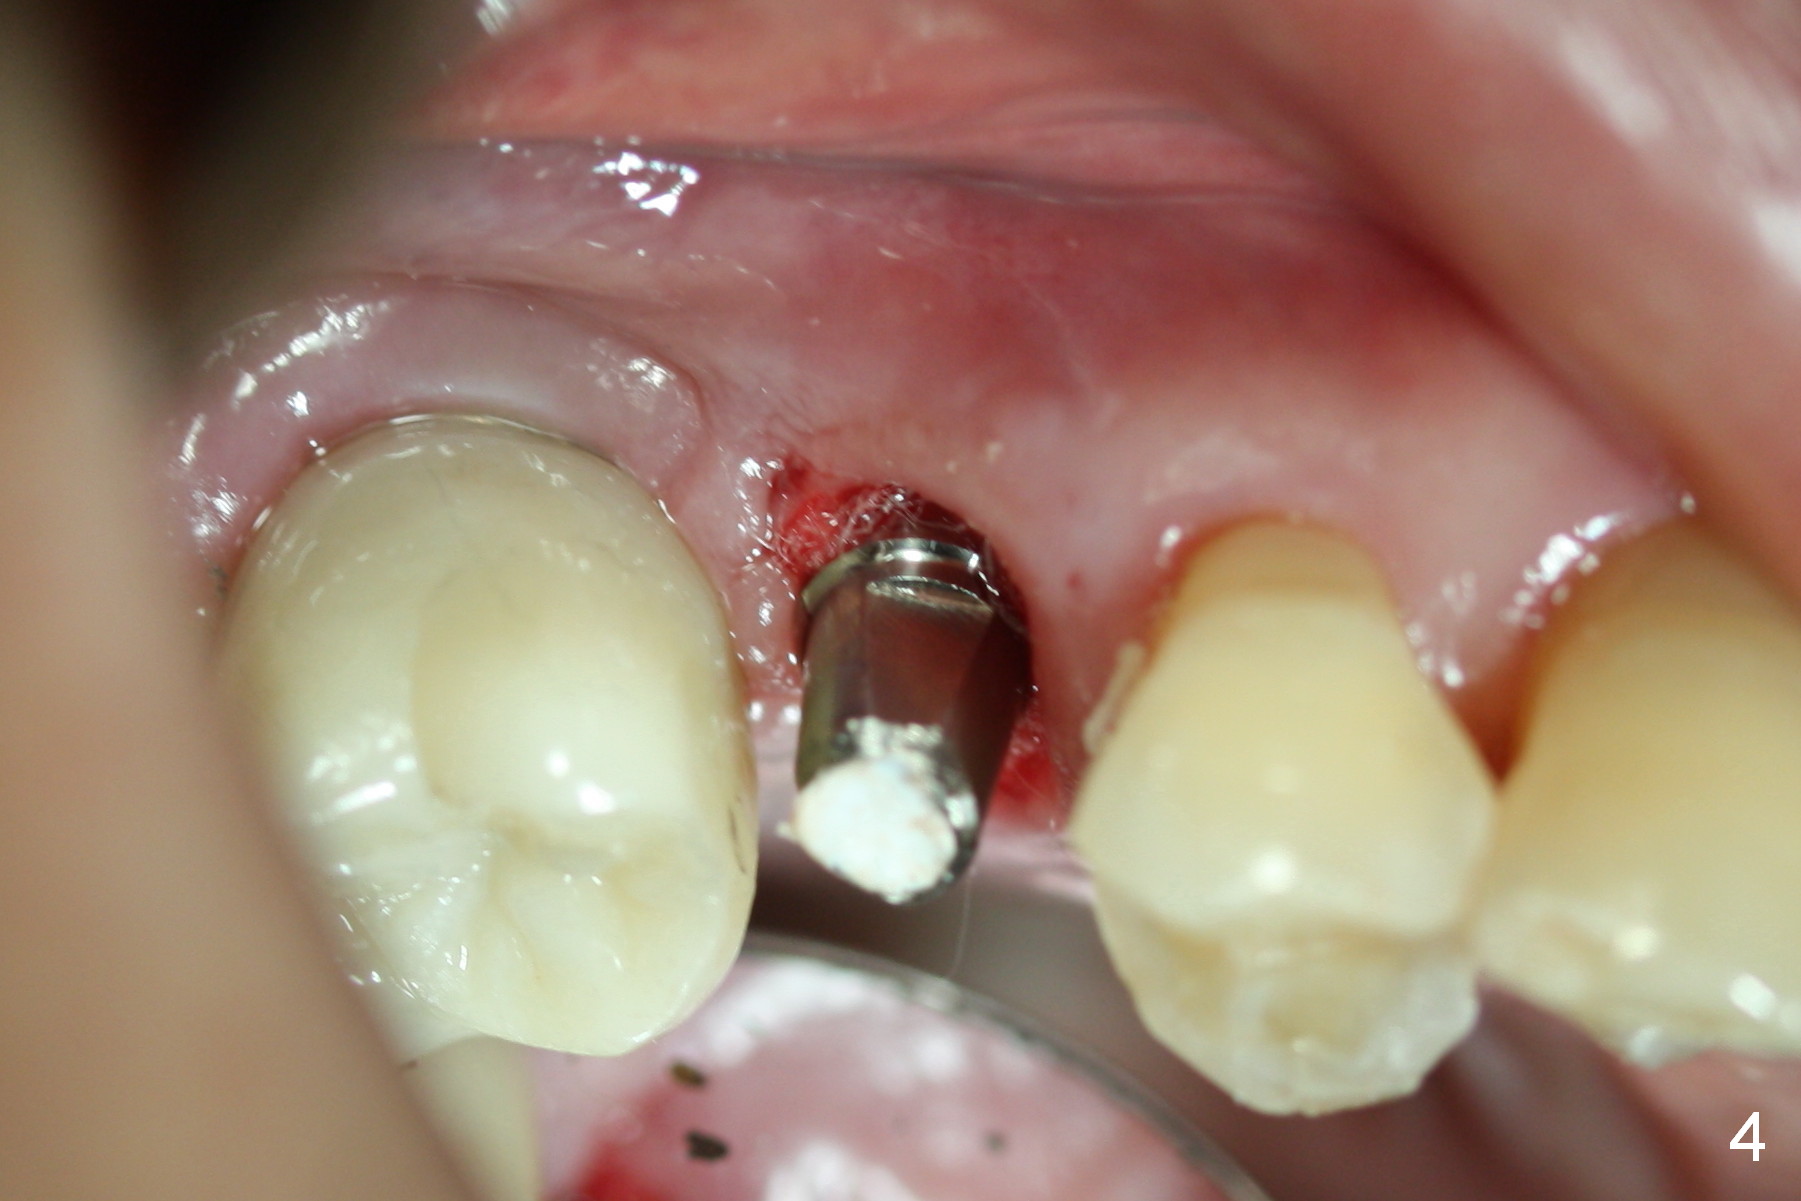

The distal buccal (Fig.1) and palatal (Fig.2) papillae (*) are recessive at the tooth #4.  Following extraction and use of 3.8 mm Magic Drill, a 4.5x13 mm implant is placed lower than the mesial crest (Fig.3) to reduce the chance of the distal implant thread exposure.  The latter is a measure to decrease peri-implantitis.  A 4.5x5.7(4) mm pair abutment is placed (Fig.4,5).  The remaining socket is filled with allograft/Osteogen placement.  The large space between #3 and 4 implants is occupied by the healthy gingiva, where bone graft cannot get in.